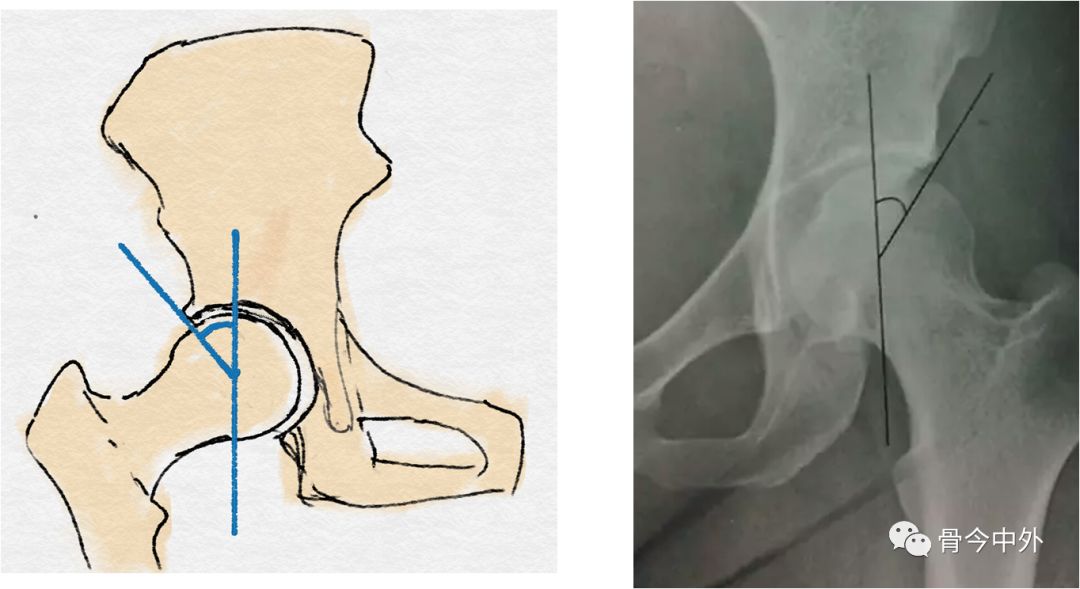

经股骨头中心的垂线与股骨头中心至髋臼外缘连线的夹角(正常:25°~40°)

CE角:即中心边缘角,股骨头中心至髋臼外上缘的连线,与股骨头中心的垂线形成的夹角。成人25°以上正常,小于20°提示DDH。